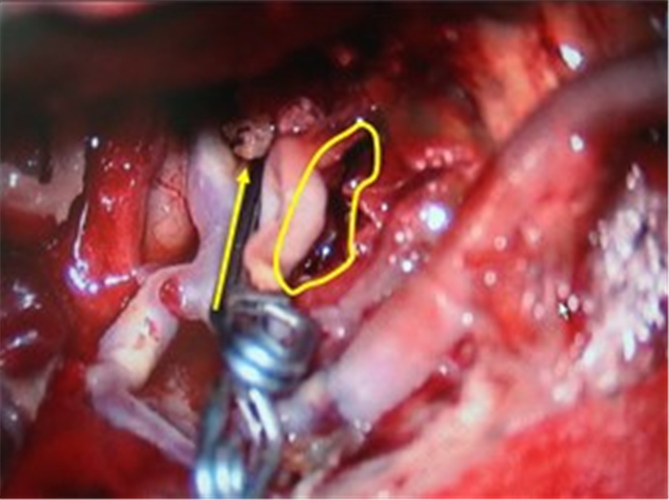

蛛網膜下腔出血引發腦血管痙攣

血管狹窄引起腦血管痙攣手術

手術治療腦血管痙攣合併動脈瘤

腦血塊導致腦血管痙攣切片

腦血管痙攣造影

腦血管痙攣手術中